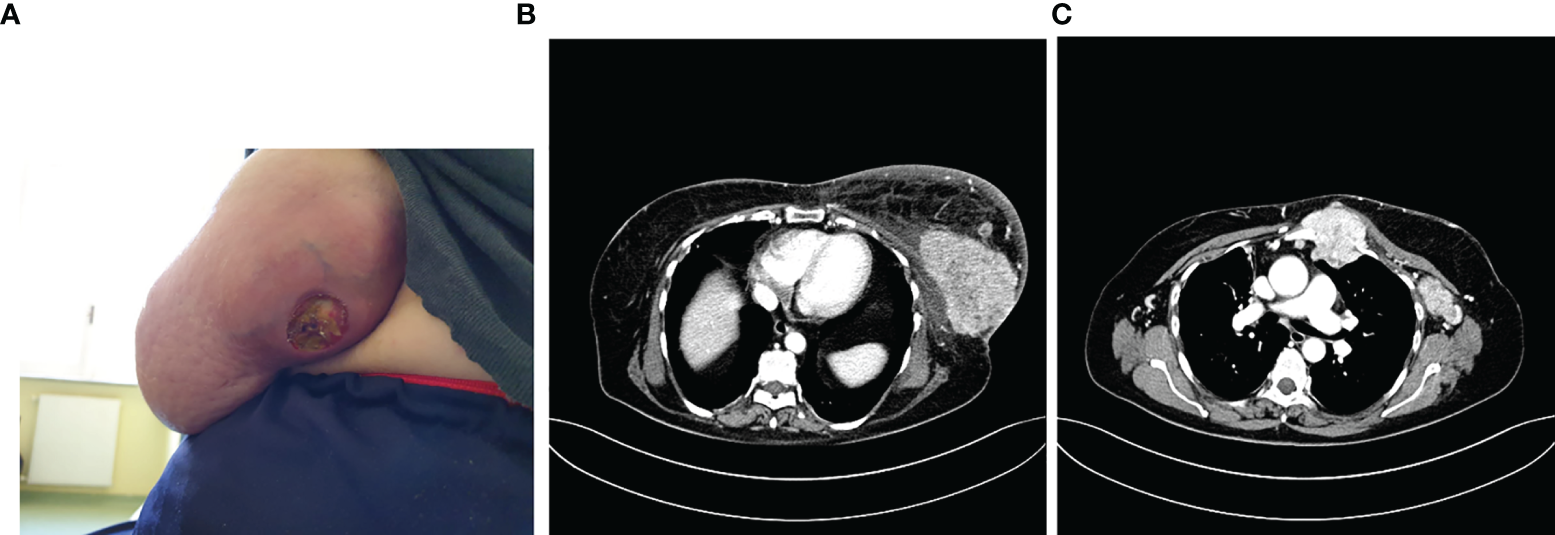

In 2010, she underwent left quadrantectomy surgery plus sentinel lymph node biopsy (SNLB) for a moderately differentiated invasive ductal carcinoma (IDC), non-specific type (NST), with ER 98%, PR 80%, Ki-67 10%, HER-2 negative, immunohistochemistry (IHC) profile (stage pT1c pN0). Therefore, she was subjected to adjuvant treatment with radiotherapy (RT) and hormone therapy (HT) with letrozole 2.5 mg for 5 years. Follow-up for relapse of disease was negative until May 2020 when it came to our attention for the first time, reporting from about 15 days of the onset of an ulcerated swelling at the level of the left breast (Figure 1A). A bilateral mammary ultrasound revealed a significant increase in the volume of the left breast, with the presence at the superior external quadrant of a hypoechoic, heterogeneous, and intensely vascularized large solid mass, of 8 cm in the maximum diameter. Some homolateral axillary lymph-adenopathies of 4 cm in diameter were also identified. The biopsy reported the presence of IDC, NST, poorly differentiated (G3), with ER 98%, PR 25%, ki67: 45%, HER-2 negative, IHC expression. PIK3CA on the circulating tumor DNA was also performed with no evidence of mutation. The CT scan described the presence of a solid mass of 10 × 6 cm at the level of the external superior left quadrants (QQEE) and nearby, another one of 12 × 14 mm. Also, the presence of a solid lesion along the vessels of the left internal mammary chain (55 × 53 cm), with necrotic-colliquative appearance, which infiltrates the ribs, sternum, intercostal muscles, and large pectoral, was reported. Further lymph nodes, with similar characteristics, are observed in the left axilla (50 × 24 mm) and posteriorly below the small pectoral (13 × 9 mm) and the large left pectoral (7 × 12 mm) (Figure 1B).

Figure 1

Photo of the ulcerated swelling at the level of the external quadrants of the left breast (A), described also at the CT scan (B) with the involvement of locoregional lymph nodes and sternum (C).

A bone CT scan confirmed the presence of a suspected area with hyper-absorbing hemline in the left part of the sternal manubrium, in correspondence with the known mediastinal neoformation described in the CT scan performed (Figure 1C).

Therefore, in June 2020 she underwent palliative radiotherapy (RT) of the sternum and then, after electrocardiography and signing of informed consent, she started a first line with ribociclib plus fulvestrant at the standard dosage. Already after the II cycle, there was a remarkable improvement in the cutaneous disease with a reduction of the underlying tumefaction (Figure 2A), up to the resolution of the ulceration after the III cycle of treatment (Figure 2B).

Figure 2

After the II cycle, the ulcerated was decreased (A), up to the III cycle when there was the cutaneous resolution of the ulcerated mass (B), with a partial response at the CT scan (C) and a complete response of pathological lymph nodes (D).

In September 2020, a CT scan showed a partial response with a significant reduction in dimension at the left QQEE (4.1 × 2.5 cm versus 10 × 6 cm of DM), skin always ulcerating (Figure 2C). Complete response of pathological lymph nodes was previously reported in the left internal mammary chain as well as a significant reduction of axillary adenopathies (13 versus 24 mm (Figure 2D). According to the objective radiological response, the treatment is still ongoing with good tolerability.